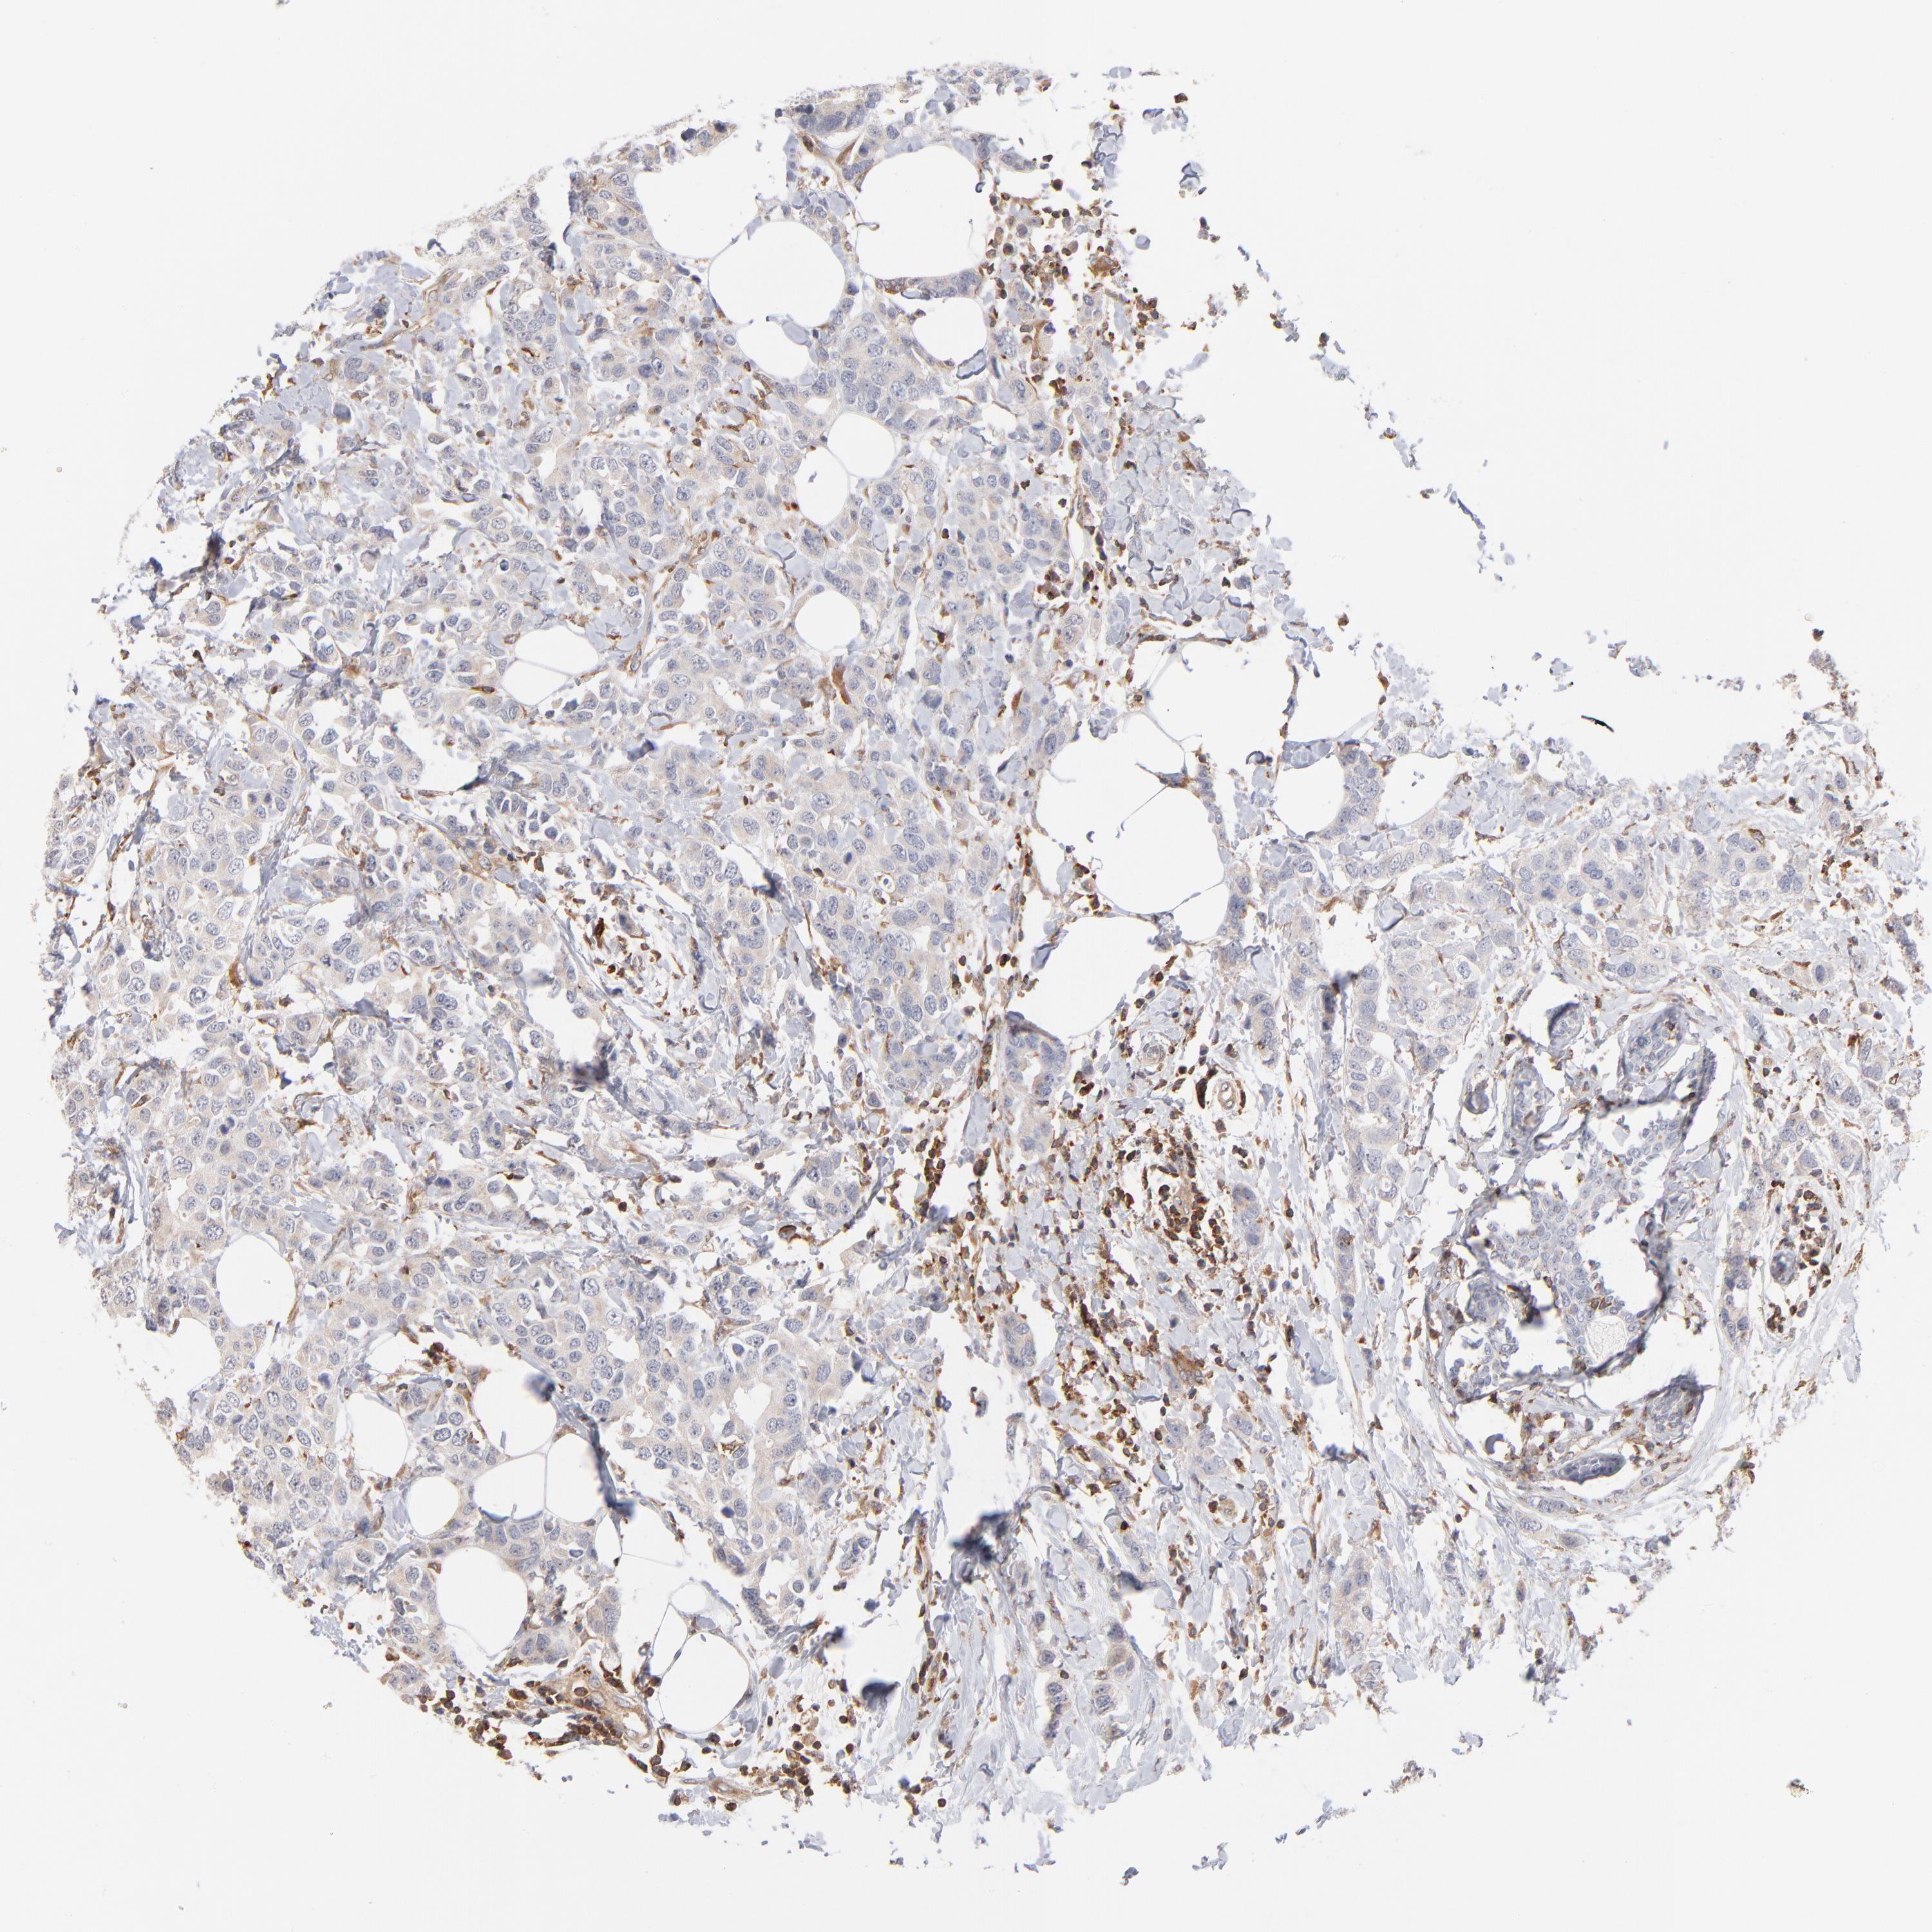

BRCA TCGA BRCA VALIDATION PROTEIN EXPRESSION

ANTIBODIES

AND

VALIDATION